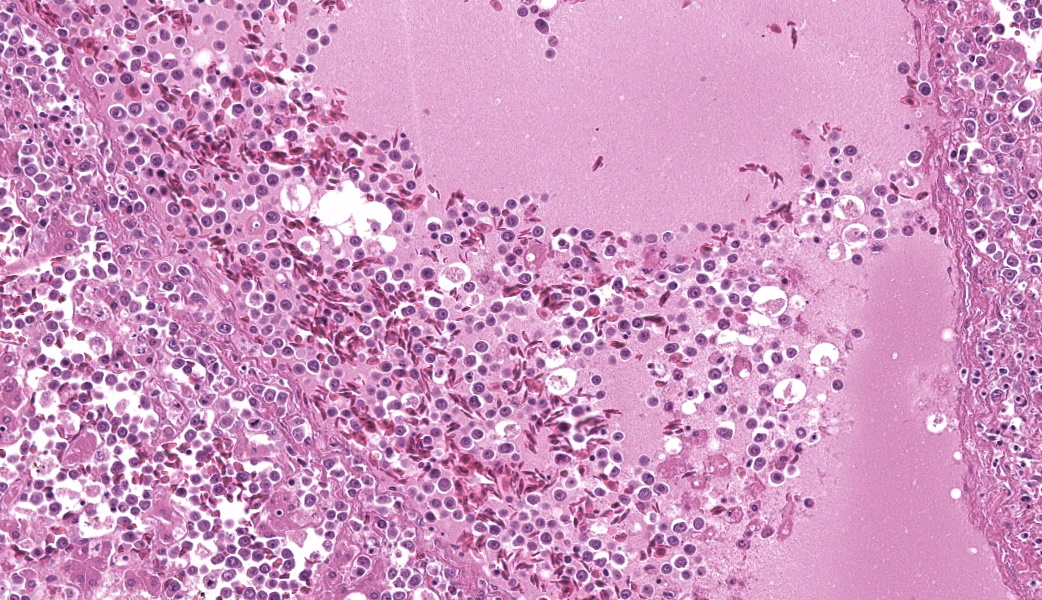

Round hematopoietic tumor cells strongly infiltrated the hepatic blood vessels and sinusoids. The hepatic sinusoids were diffusely expanded by tumor cell infiltration, with fewer normal erythrocytes and enlarged Kupffer cells which sometimes contained cellular debris. Most hepatocytes were shrunken. A few granulocytes were also found in the hepatic sinusoid. Small foci of granulocytic cells at different nuclear maturation stages were present around some hepatic triads. Tumor cells appeared round, oval, or polygonal in shape with a distinct cell border, amphophilic cytoplasm, anisocytosis, and anisokaryosis. Some tumor cells contained perinuclear pale areas known as halos. The nucleus was round and hyperchromatic to pale, with one or two large nucleoli and coarsely clumped chromatin. Some binuclear tumor cells were also observed. There was significant mitosis and karyorrhexis of tumor cells. The cytoplasmic eosinophilic granules that are characteristic to myelocytic lineage cells were not present in tumor cells.Immunohistochemical analysis revealed that tumor cells consistently exhibited cytoplasmic staining of hemoglobin antigen, with variable staining intensity, faint to strong, depending on the tumor cell. Hemoglobin was also detected in normal erythrocytes. Tumor cells were negative for CD3 (T cell marker), BAFF-R (B cell marker), and Iba-1 (macrophage/monocyte marker). Enlarged Kupffer cells were positive for Iba-1.

Tumor cells were observed in other organs, but only in the blood vessels. Some thrombi composed of necrotic tumor cells and fibrin were also observed in the vessels. The bone marrow was not histologically examined.

- Liver: Extramedullary hematopoiesis, chronic, periportal, moderate.